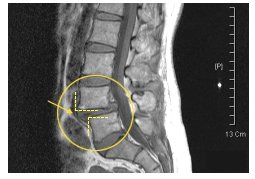

프롤로 주사치료요법 허리협착증에주사치료란